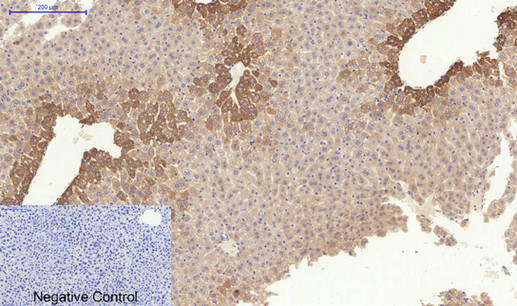

Immunohistochemical analysis of paraffin-embedded Mouse-liver tissue;

1.COL1A2 Polyclonal Antibody was diluted at 1:200(4℃,overnight);

2.Sodium citrate pH 6.0 was used for antibody retrieval(>98℃,20min);

3.Secondary antibody was diluted at 1:200(room tempeRature, 30min). Negative control was used by secondary antibody only.